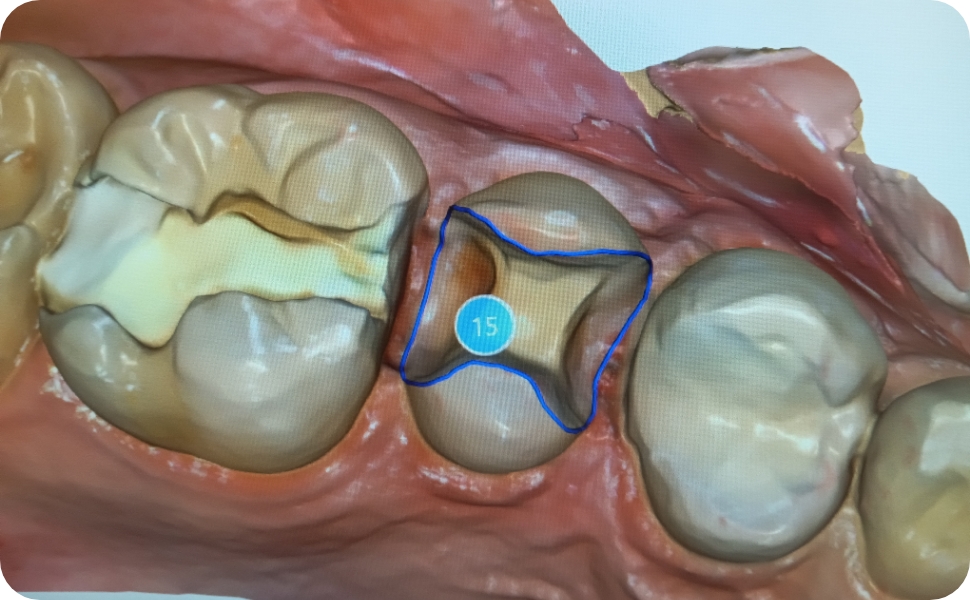

虫歯の治療は虫歯が深いか?浅いか?どの部位のあるか?によって治療の流れや方法が変わってきます。

基本的な特徴としては浅くて小さい虫歯は処置回数も少なく、時間も費用もそれほどかからなく見た目の目立たなく終わる傾向にあります。

逆に深くて広範囲の虫歯ほどより多く削らなければならないため、処置回数が多くなり時間も費用もかかり見た目が目立つ傾向にあります。

噛む面の部分の浅い小さい虫歯

1,必要に応じて麻酔を行い十分麻酔が効いた後虫歯を専用のドリルで削って除去していきます。

除去に使用する切削器具はいろいろあり歯の状態によって都度切削器具を変えて虫歯をとっていきます。

途中痛みが出たりするようであれ麻酔を追加で入れたりしていきます。なるべく虫歯だけを取り除き最小限の切削で処置していくのが理想ですが取り残さないのが一番大事なことになります

2,削った部分にCRと言われる白い樹脂を入れていきます。

まず表面をエッチングと呼ばれる専用の薬剤で10秒処理洗浄していきます。

その後専用の接着剤であるボンでイング材をを塗布し、この材料を10秒から20秒光をあてて表面性状を変えて、くっつきやすくしていきます。

イメージとしてはお化粧の、のりをよくするために下地を作る作業と似ています。

3,白い樹脂(CR)を詰めて硬化処理します。

白い樹脂はCRと呼ばれるプラスチックのものですがほかの業界としては、ネイルサロンとかでも似たようなものが使われています。

作業もほぼ一緒で光で固まる色とりどりの樹脂で、デザインしていくのと同じです。

なのでCRが好きな先生は「白いキャンパスに絵を描いていくよう」と表現する先生もいます。

4,硬化させたのち噛み合わせを調整して研磨して終了です。

硬化後噛み合わせや形態を専用のドリルを使って修正していきます。

そうしなければ結局のところ機能性がなく意味がなくなるので審美的、機能的に処理しようと思うとこの工程が一番重要と言われる先生もいます。

ネイルでいえば最後の磨きに相当する処置になります。